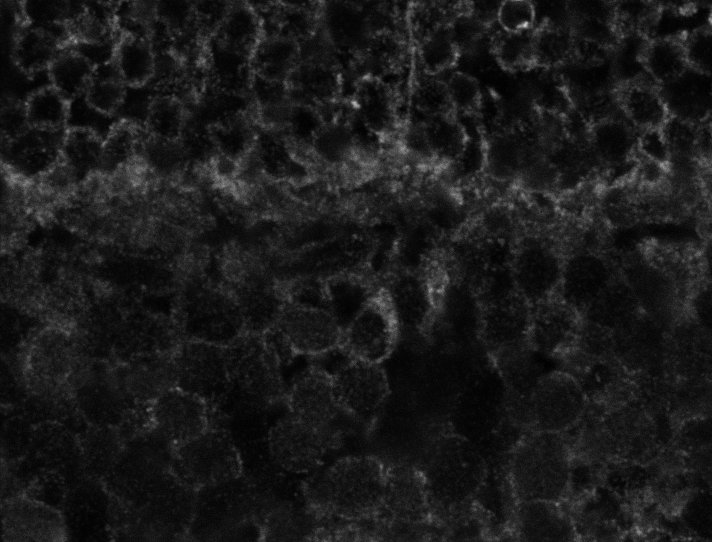

Healthy Choroid

Unhealthy Choroid